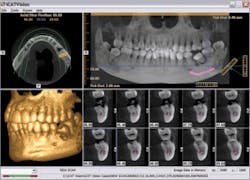

A patient with a previously grafted alveolar cleft was recently referred to our clinic by another surgical practitioner for implant placement. While the referring practitioner indicated that the grafted area was an acceptable recipient site based on available 2–D imaging, the cone beam scan showed grossly insufficient bone into which to place the implant. This is clearly evident on the images (Fig. 1, 2). If implant surgery had been instituted based on the information provided by the 2–D images, without this additional and vital information, the patient's confidence could have been lost, as well as potential referrals to his friends and family, possibly causing a negative impact to ROI. In this case, however, a 3–D computer model clearly pointed out the bony deficiency prior to surgery.

Specialized 3–D reconstructive software also allows practitioners to provide 3–D images and viewer software to the referring dentist, allowing for collaboration regarding positioning, placement, and angulation of implants prior to surgical placement procedures (Fig. 3).